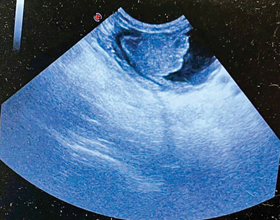

Using ultrasound in the ER setting

Explore key techniques and the advantages of using ultrasound in urgent care, focusing on its role as a rapid screening tool for abdominal scans in emergency situations.